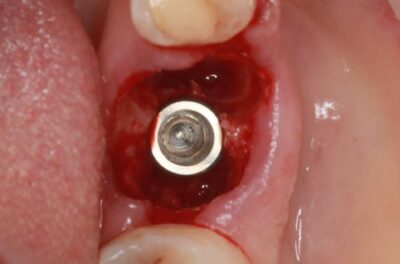

Специализация: терапия(эндодонтия), ортопедия, имплантология.